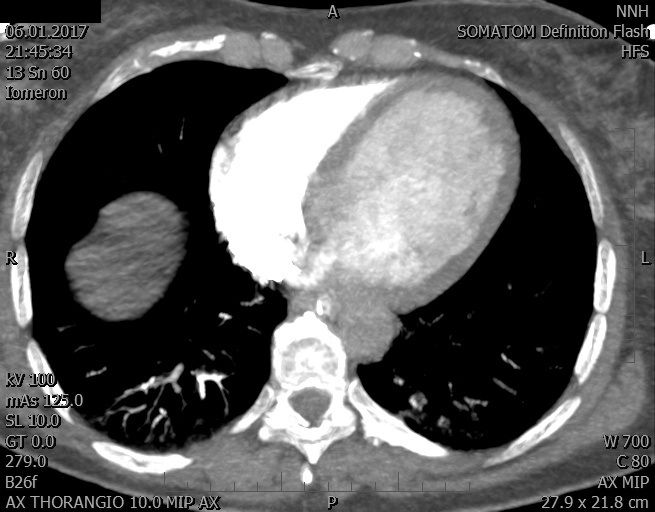

Video 2 - Echokardiograficky byla zjištěna těžká dysfunkce dilatační levé komory s nezvětšenou pravou komorou.Pro nejasnou příčinu zástavy jsme provedli i vyšetření výpočetní tomografií (CT), které vyloučilo plicní embolizaci (série 1 - soubory na konci článku). V den přijetí při přetrvávající oběhové nestabilitě byla nemocná opakovaně defibrilována pro fibrilaci komor se stabilizací rytmu po podání amiodaronu a mesocainu. Dle hemodynamických měření se jednalo o těžký kombinovaný šok. Vstupní laboratorní vyšetření bylo bez větších pozoruhodností. Posléze jsme doplnili anamnézu od příbuzných a zjistili, že pacientka užila do dvou hodin před srdeční zástavou první tabletu amoxicilinu na lehký respirační infekt. Při nevýtěžnosti vstupních vyšetření a nových anamnestických informacích jsme doplnili 14 hodin po kolapsu vyšetření koncentrace tryptázy v séru, která byla extrémně zvýšena (tabulka 2), což nás vedlo k podezření na anafylaxi.